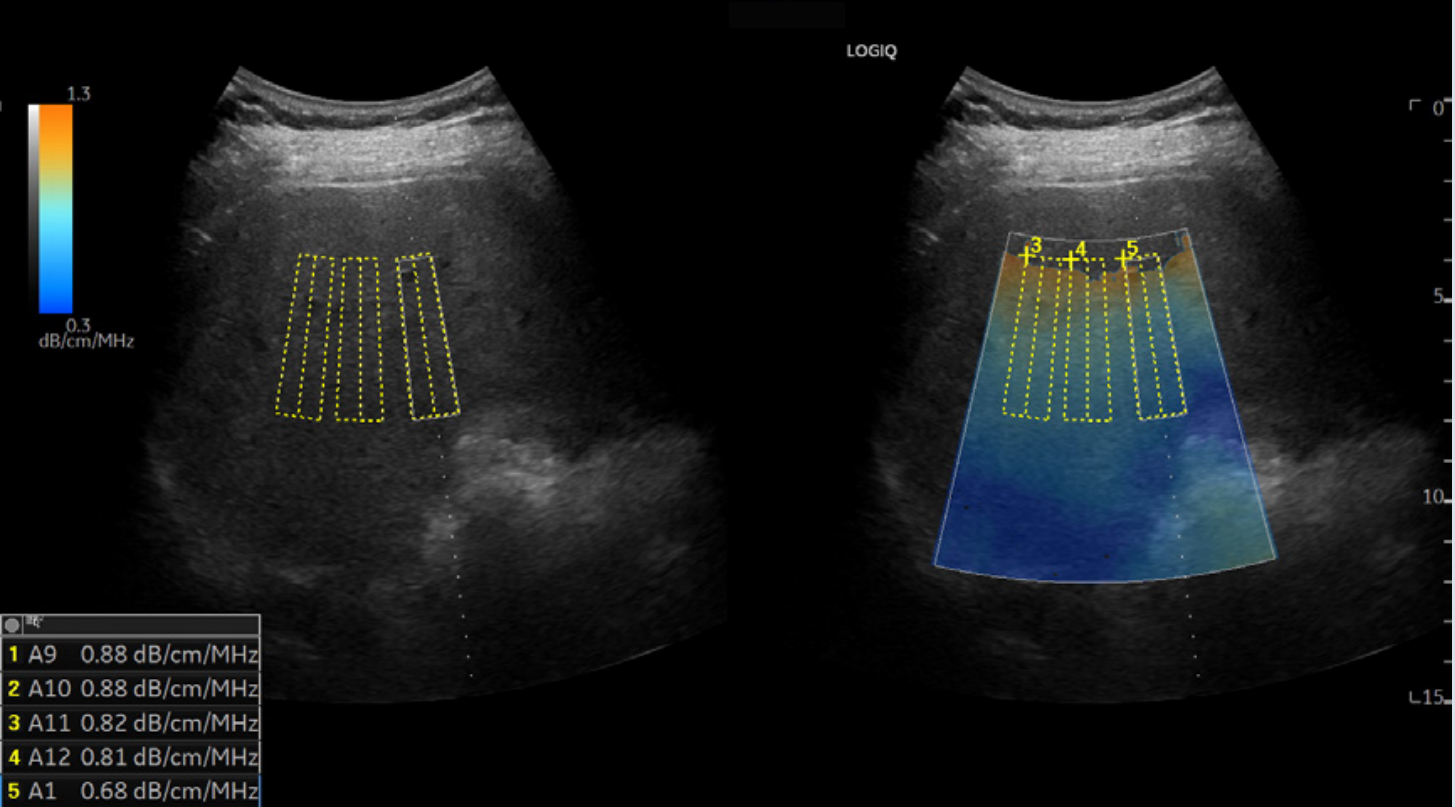

UGAP声衰减成像:

脂肪变性细胞含量的多少影响声衰减的程度。UGAP声衰减成像是基于原始射频信号,利用先进算法定量超声波在组织内的衰减程度,从而获得组织的衰减系数或衰减率。UGAP用于脂肪性肝病进行无创精准定量分级,对肝脏脂肪变性的早期发现、评估和监测具有重大意义。

声衰减图:

用颜色显示区域衰减值

避开大血管、大反射界面